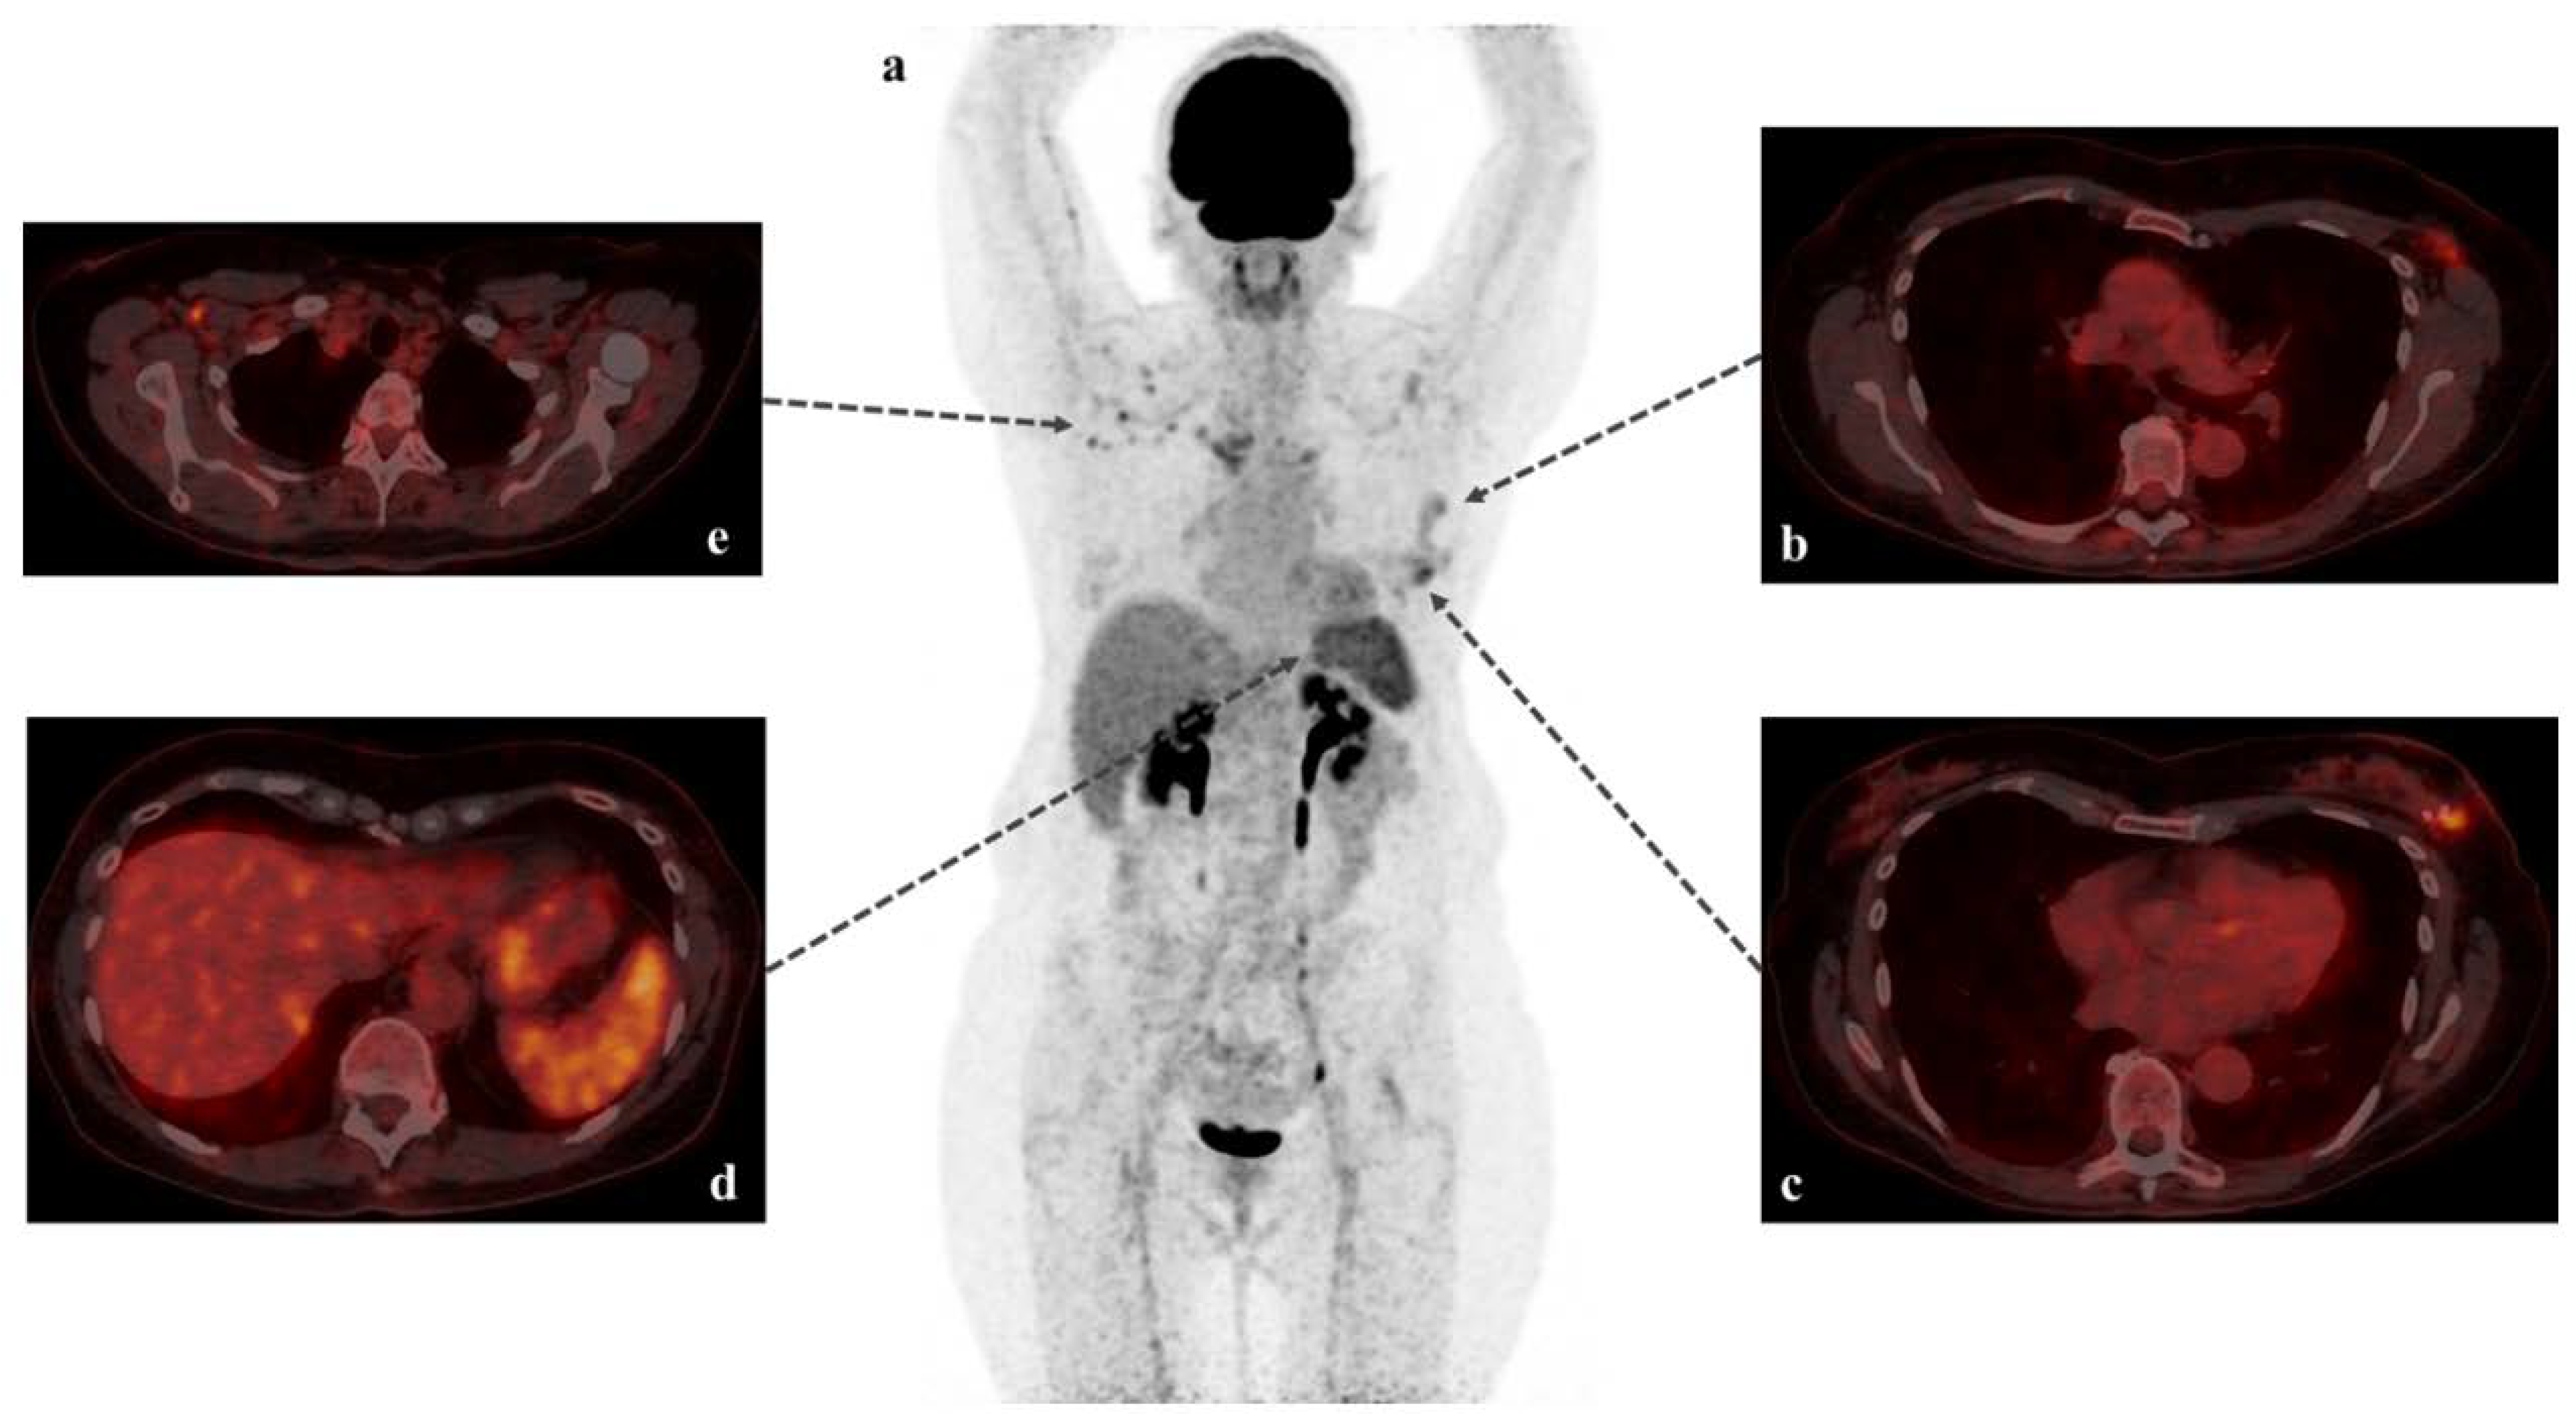

Immune Response Visualized In Vivo by [18F]-FDG PET/CT after COVID-19 Vaccine